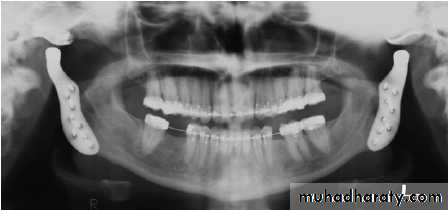

Radiology

it is not specific!

# Radiology demonstrates reduction in bone density in the TMJ.

# Marked erosion of the condylar head and articular fossa.

# Narrowing of the joint space.

In long-standing disease, there is:

• destruction of entire condyle• anterior open bite

• secondary osteoarthrosis

• ankylosis.

1. Arthroplasty for total joint replacement